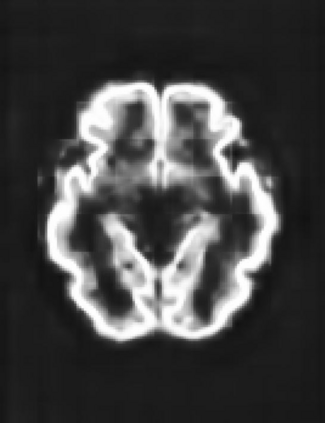

Fetal cortical plate segmentation is essential in quantitative analysis of fetal brain maturation and cortical folding. Manual segmentation of the cortical plate, or manual refinement of automatic segmentations is tedious and time-consuming. Automatic segmentation of the cortical plate, on the other hand, is challenged by the relatively low resolution of the reconstructed fetal brain MRI scans compared to the thin structure of the cortical plate, partial voluming, and the wide range of variations in the morphology of the cortical plate as the brain matures during gestation. To reduce the burden of manual refinement of segmentations, we have developed a new and powerful deep learning segmentation method. Our method exploits new deep attentive modules with mixed kernel convolutions within a fully convolutional neural network architecture that utilizes deep supervision and residual connections. We evaluated our method quantitatively based on several performance measures and expert evaluations. Results show that our method outperforms several state-of-the-art deep models for segmentation, as well as a state-of-the-art multi-atlas segmentation technique. We achieved average Dice similarity coefficient of 0.87, average Hausdorff distance of 0.96 mm, and average symmetric surface difference of 0.28 mm on reconstructed fetal brain MRI scans of fetuses scanned in the gestational age range of 16 to 39 weeks. With a computation time of less than 1 minute per fetal brain, our method can facilitate and accelerate large-scale studies on normal and altered fetal brain cortical maturation and folding.